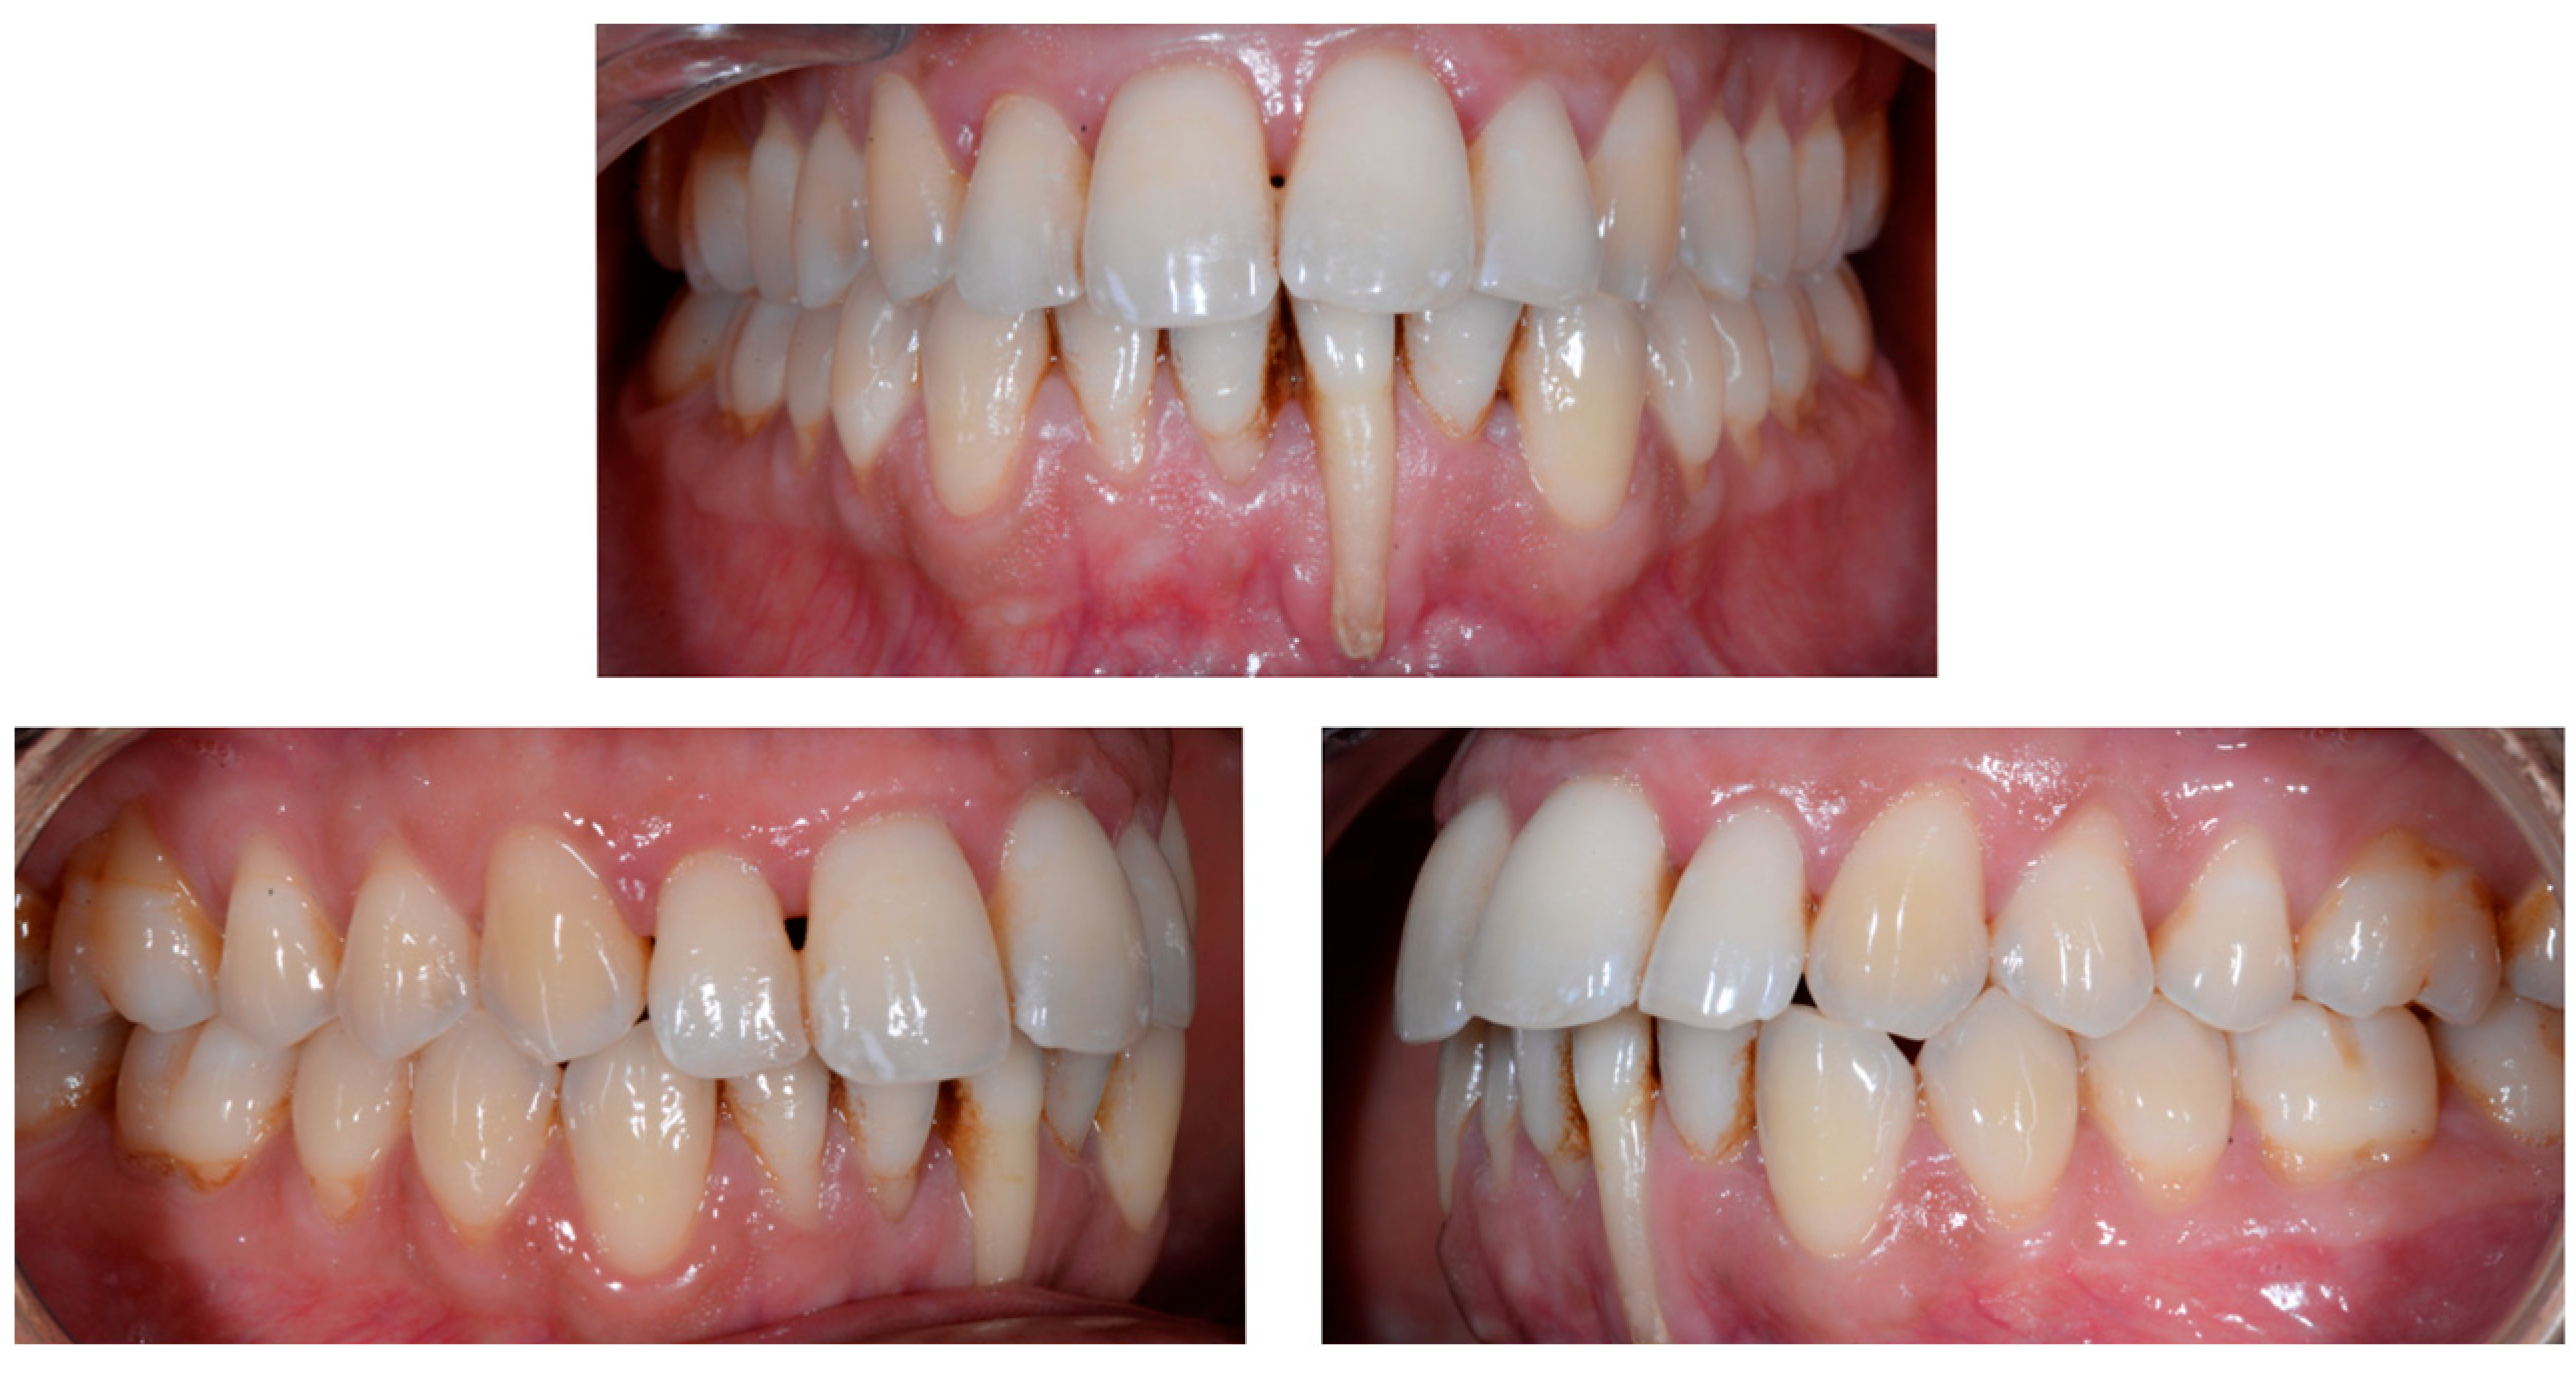

A 26-year-old female patient was referred by her general dentist for suspected wire syndrome. Orthodontic treatment had been performed 10 years previously, and bonded restorations had been fitted at the end of the treatment. The patient mentioned several episodes of breakage/adhesion, without further details. She has good oral hygiene and a right and left Class I (Figure 5).

Figure 5.

Intermediate wire syndrome. Frontal and lateral views.

In Figure 6, 11 and 21 show a difference in incisal edge height and gingival margin. Tooth 41 shows gingival recession to the muco-gingival junction (Cairo’s RT1) with root visibility. Tooth 33 had a significant lingual tilt (coronal–lingual torque), not symmetrical to tooth 43.

Figure 6.

Intermediate wire syndrome. Frontal view.

The root of tooth 21 is visible through the gingiva (Figure 7). Figure 8 shows the extent of gingival recession on tooth 41.